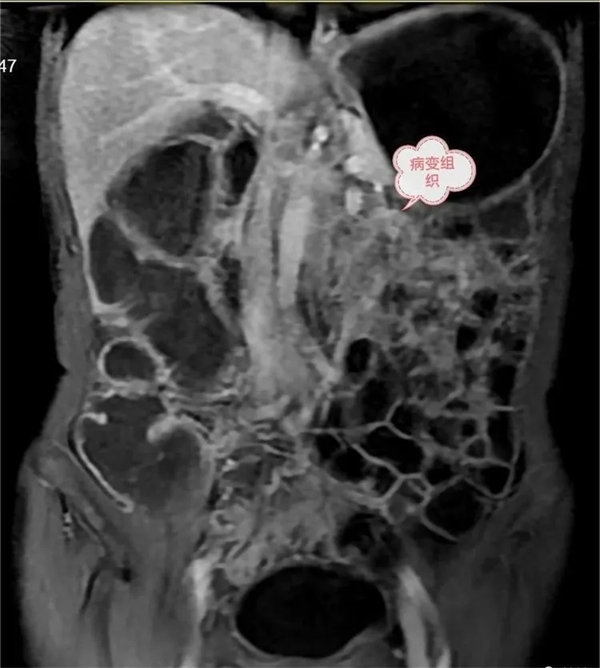

圖3:延遲期,顯示腸系膜根部病變逐漸輕度強化。胃,結腸充盈顯示良好,腸壁強化,未見異常。

圖4:磁共振功能成像清晰顯示病變DWI呈明顯高信號,ADC圖呈低信號,腹膜后多發小結節灶。

圖5:DWI腫瘤呈明顯高信號,ADC圖呈低信號,中心為被包繞的腸系膜血管。